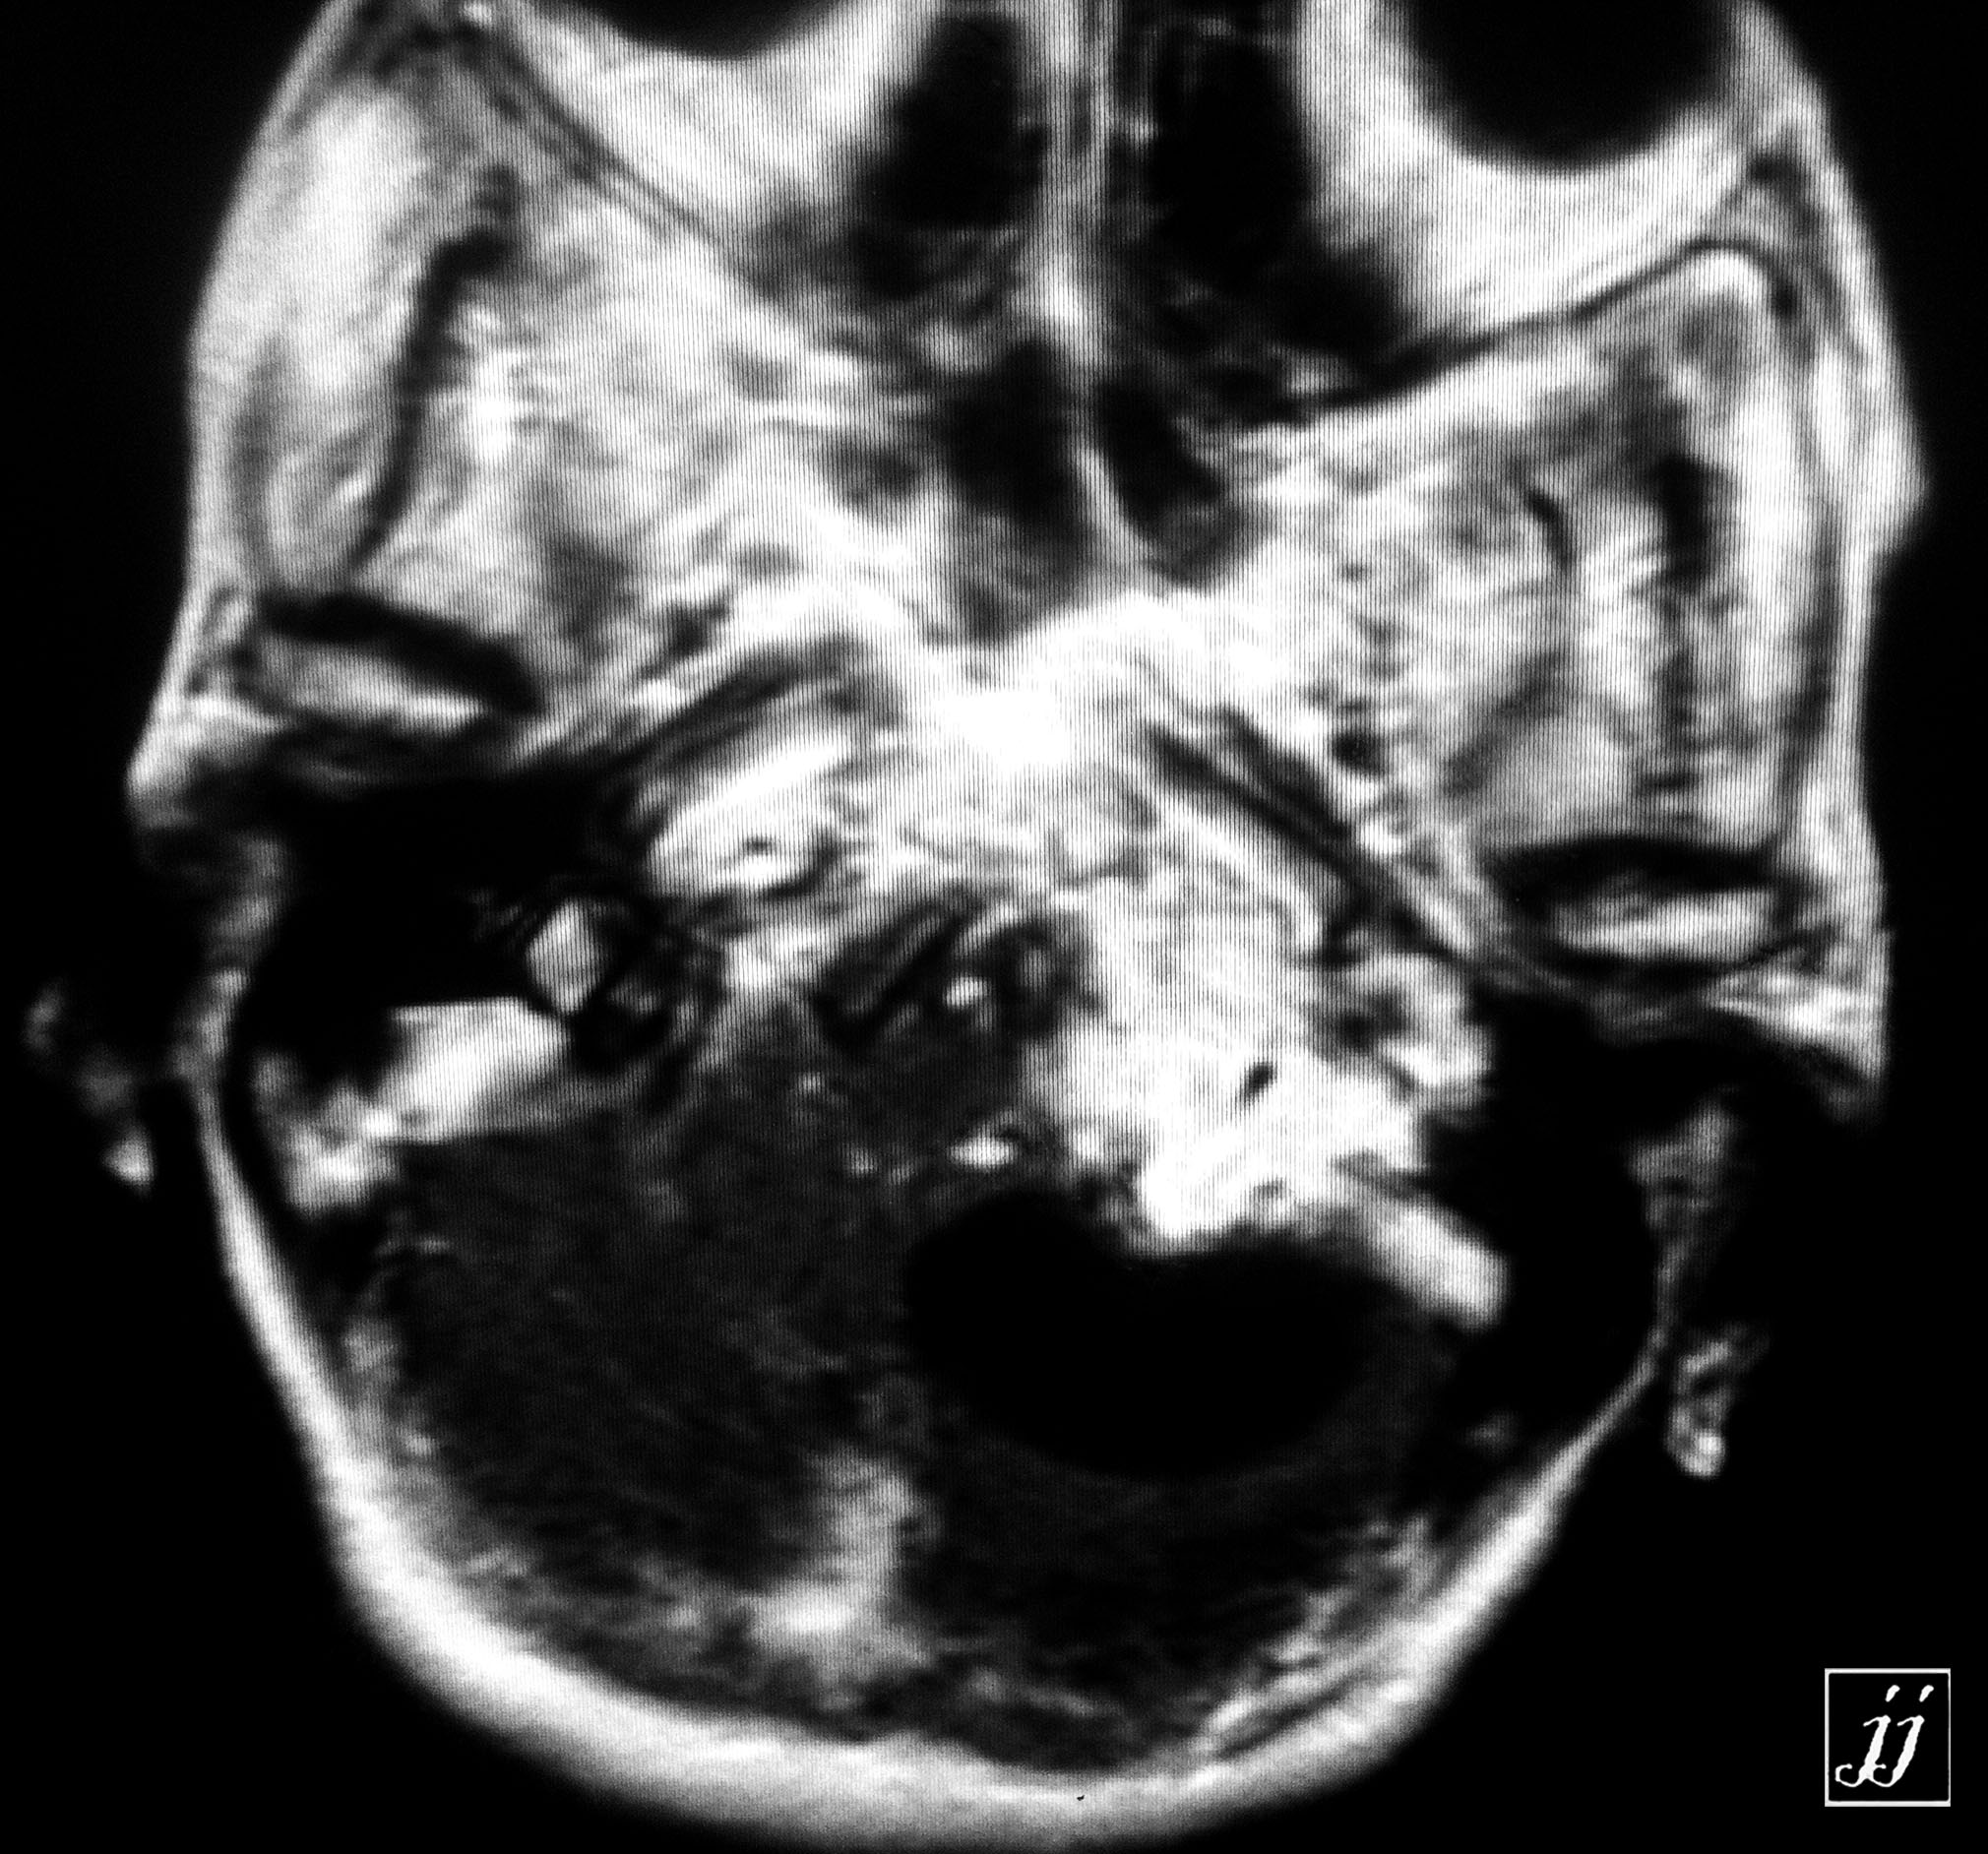

Brain- CPA tumor (10)